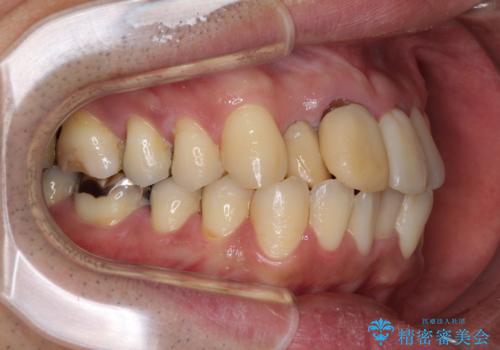

仕事柄海外出張が多いとのことで、インビザラインにて矯正治療を行うこととしました。

矯正治療後は、前歯や下顎の奥歯など、むし歯治療途中の歯をオールセラミッククラウンにて補綴治療を行うこととしました。

治療途中で海外に長期滞在することとなり、5年近く帰国することができなかったため、治療期間は非常に長いものとなりました。

内側に転位していた前歯は、矯正治療では治しきることができませんでしたが、幸いにもオールセラミッククラウンに置き換える予定であったため、希望通りの仕上がりとなりました。